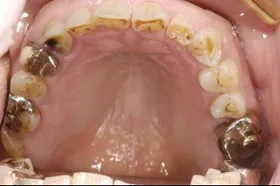

金属を白くし、歯茎の黒ズミを改善したケース

■治療前

■治療後

| 主訴 | 全体的に白い歯にして見た目をきれいにしたい 歯茎が黒くなっているのが気になる、歯ならびも良くしたい |

|---|---|

| 治療方法 | 矯正治療+歯茎の黒ずみの改善+補綴治療 |

| 治療期間 | 3年 |

| 通院回数等 | 約40回 |

| 費用 | 約350万円 |

| リスク・副作用 | 矯正治療も行ったので治療期間が長くなった |